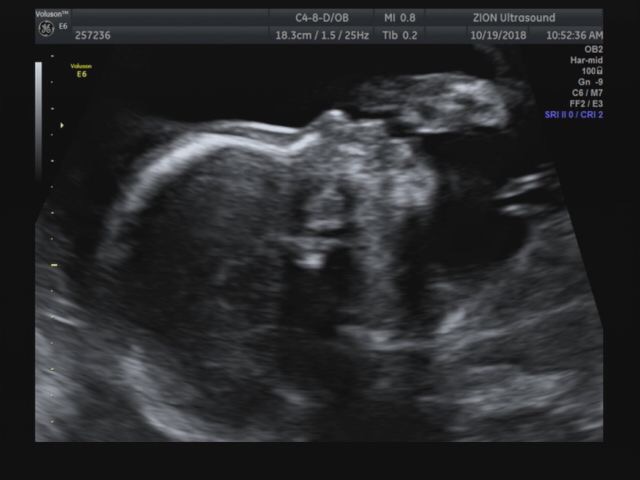

임신 32주3일 태동검사

지난 임신 29주에 입체초음파보구 3주 뒤인 32주 3일차에 태동검사+정기검진 다녀왔다 보통 28주 이후부터...